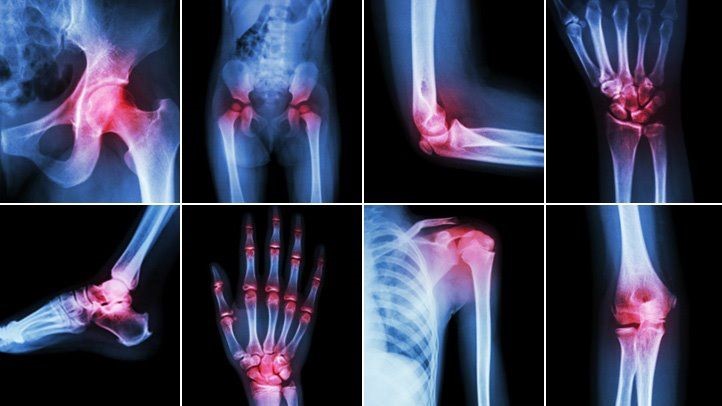

Vị trí khớp tổn thương trong viêm đa khớp dạng thấp